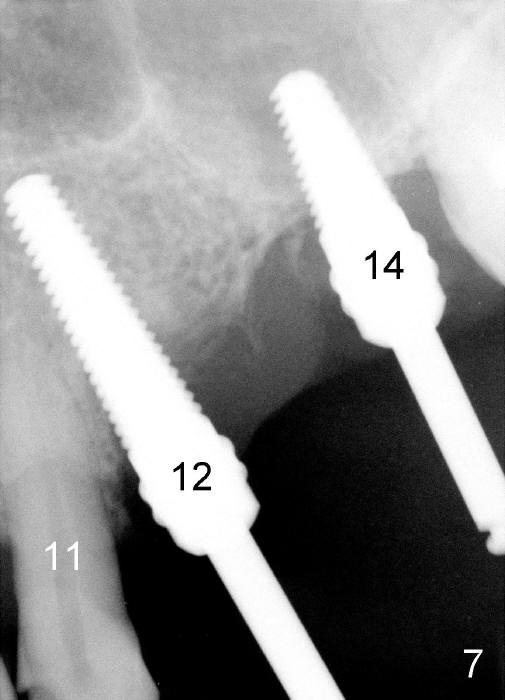

Initially the osteotomy is established with drill/reamers alternated with taps in the septum near the palatal socket. When a 4.5x14 mm tap (Fig.6 T; Fig.7: #14) is inserted, the sinus floor is perforated, but the sinus membrane is intact. When 7x14 mm tap is inserted, the sinus membrane is perforated in the buccal aspect of the osteotomy. The latter is repaired by placement of collagen dressing and then bone graft and membrane again (sandwich). The osteotomy is shifted to the palatal socket by using 5x14 and 6x14 mm taps. When the last tap is removed, the small area of the buccal aspect of the osteotomy is also found to be perforated, but the membrane is intact. When a 6x14 mm implant is placed (Fig.8), the coronal end is close to the middle of the socket (buccopalatally, due to angulation of the palatal socket).

Placement of immediate implant at the site of #12 is relatively easy. Adjustment is more or less mesiodistal. A 2 mm pilot drill (Fig.6 P) is found close to the root of the tooth #11 (red dashed line). The osteotomy is then moved distally (Fig.6 arrow). When 4.5x20 mm tap (Fig.7: #12) and 4.5x17 mm implant (Fig.8 I) are placed, there is distance from the root of the neighboring tooth. Insertion torque of the both implants is >60 Ncm. Abutments are placed (A in Fig.8) for immediate provisional.